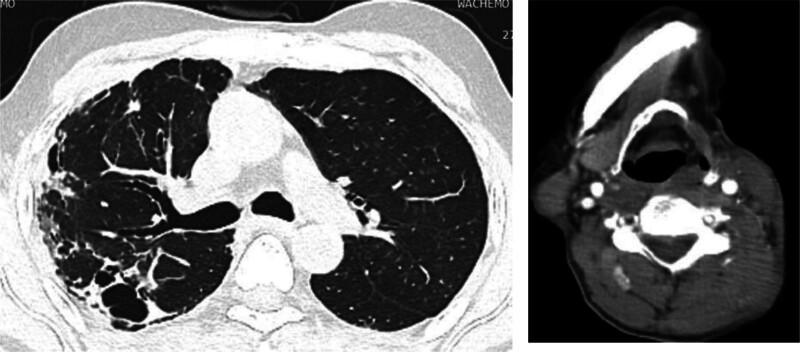

A 55-year-old man presented with neck pain and swelling that had persisted for 1 week, following 2 weeks of blunt trauma to the head and neck, which resulted in several superficial abrasions due to his poorly managed epilepsy. Imaging studies revealed thrombosis in the left IJV, accompanied by an abscess that extended into the sternocleidomastoid muscle. Gram staining of the specimen obtained from the neck abscess confirmed the presence of Streptococcus bacteria.

The presence of a thrombus in the IJV following blunt trauma to the head and neck, along with a nearby soft tissue abscess, suggests a diagnosis of LS. However, this case is atypical due to the unusual preceding event of blunt trauma and the identification of a rare pathogen, specifically Streptococcus bacteria.

The patient received 2 weeks of intravenous antibiotic treatment with ceftriaxone and metronidazole, followed by 2 additional weeks of oral amoxicillin-clavulanate. Additionally, approximately 100 mL of foul-smelling pus was evacuated from the neck region.